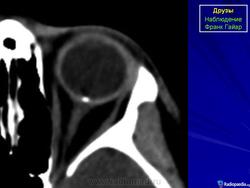

При КТ-исследовании изредка попадаются больные с наличием у них в области диска зрительного нерва плотных включений, которые могут быть приняты за инородные тела. Это так называемые друзы. Друзы диска зрительного нерва – довольно редкое заболевание, характеризующееся гроздевидными округлыми возвышениями над диском нерва, состоящими из гиалина. Иногда в них откладывается известь. Считают, что друзы имеют наследственный характер.

КТ-семиотика

При КТ друзы отличаются локализацией – только в диске зрительного нерва, небольших размеров (не более одного миллиметра) и правильной округлой формы. Друзы совершенно однородны, не дают артефактов и имеют определенную плотность (150-200 НU).